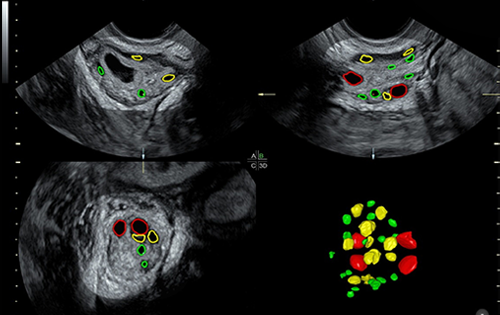

Advanced ultrasound, screening, and diagnostic services for accurate fetal and maternal health assessment.

She topped the Punjab PG entrance exam and went ahead to pursue MD in Radiodiagnosis from Dayanand Medical College, Ludhiana. During her training, she got interested in the field of fetal medicine and did fellowship in fetal imaging from Mediscan Systems Chennai.